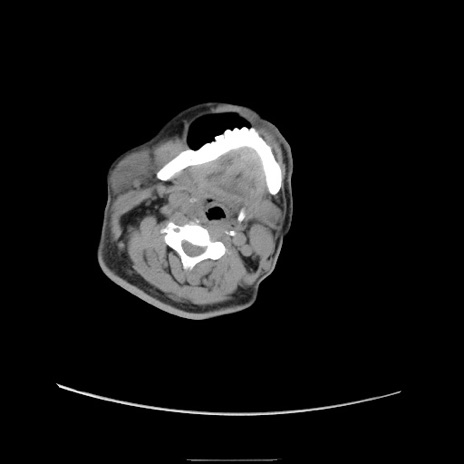

症例22(横断像)

【症例】50歳代男性

【主訴】腹痛

【現病歴】AVMからの被殻出血のため回復期リハ病棟入院中。 本日午後3時頃急に下腹部痛が出現した。

【既往歴】AVM、被殻出血、虫垂炎、高血圧

【身体所見】意識晴明、左半身不全麻痺、会話の理解は良好、36.5°C、腹部:膨隆、全体に板状硬、下腹部正中に圧痛点あり、反跳痛-、筋性防御不明、右下腹部にope scar

【データ】WBC 9400、CRP 0.06